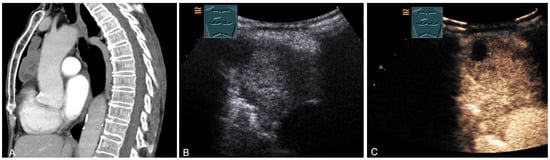

A cystic mediastinal mass on CT (provided by Prof. Dr. Andreas H. Mahnken, Marburg, Germany) (A), B-mode US (B), and CEUS (C), surgically confirmed as a mediastinally located bronchogenic cyst.

Figure 15.

An echogenic mediastinal mass as an incidental finding on CT (provided by Prof. Dr. Andreas H. Mahnken, Marburg, Germany) (A), B-mode US (B), and CEUS (C), evaluated by imaging as a retrosternal located thyroid gland.